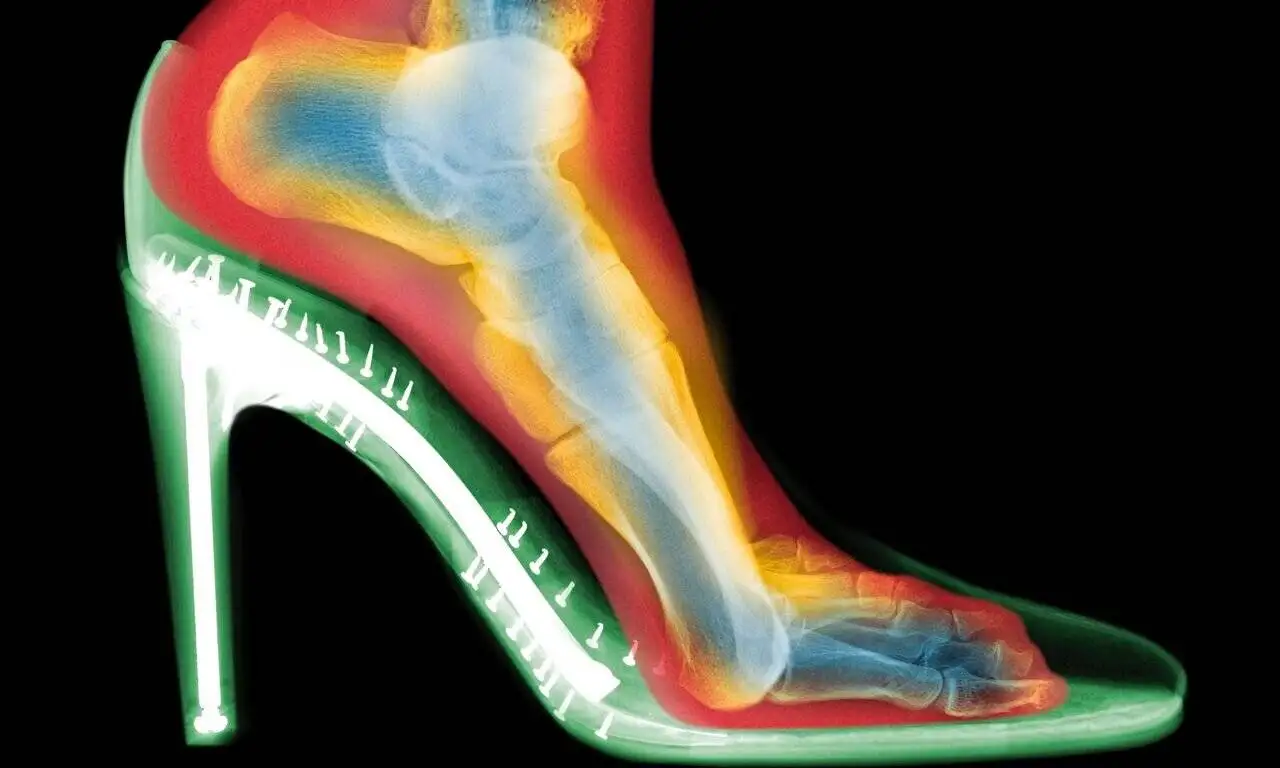

به گزارش سرویس مجله وبپیما به نقل از همشهری - پوشیدن مداوم کفش های پاشنه بلند می تواند به تغییر شکل دائمی پا، ایجاد قوز شست و آرتروز منجر شود. یک متخصص ارتوپد که پیش تر این ایده را رد می کرد، امروز با مشاهده اسکن های سه بعدی هشدار جدی می دهد.

«اگر ۱۵ سال پیش از من می پرسیدید، می گفتم کاملاً بی معناست؛ همه چیز ژنتیکی است و کفش ها مسئول هیچ مشکلی نیستند.»؛ این را اندرو گلدبرگ (Andrew Goldberg)، متخصص ارتوپدی پا و مچ پا در بیمارستان ولینگتون لندن می گوید. اما او پس از دیدن اسکن های سه بعدی از پاهای افراد در حین پوشیدن کفش، نظر خود را کاملاً تغییر داد.

اسکن های سه بعدی چه نشان دادند؟

گلدبرگ دو اسکن از پای یک فرد تهیه کرد: یکی بدون کفش و دیگری با کفش پاشنه بلند. تفاوت ها چشمگیر بود:

فشردگی انگشتان : انگشتان پا در کفش به هم فشرده شده بودند؛

انحراف شست پا (بونیون) : مفصل انگشت شست به طرف بیرون متمایل شده بود؛

انگشتان چنگالی : انگشتان کوچک تر برای حفظ تعادل، حالتی قفل شده و خمیده به خود گرفته بودند.